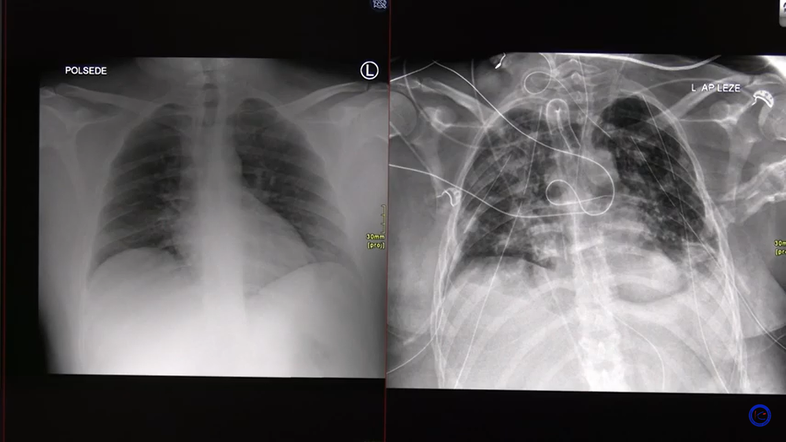

Rentgenska slika pljuč Youtube/prtscr

Dva primera covid pljučnice - pri enem bolniku se je stanje relativno hitro izboljšalo, drugemu, le 30-letnemu bolniku, pa so morali presaditi pljuča.

Zdravnik Matjaž Turel je s pomočjo rentgenskih in CT posnetkov predstavil dva primera potekov covid pljučnice. Kot je pojasnil, se pri 90 odstotkih bolnikov pljuča lepo popravijo. A vseeno se lahko zaplete.

Pri prvem bolniku na rentgenski sliki sprva ni bilo videti kakšnih velikih sprememb, le nekaj meglic. Le štiri dni po tem pa je prišlo do poslabšanju stanja. Bolnik je prejemal kisik, a so se meglice začele gostiti, po obeh pljučnih krilih so se pojavili madeži, ki so dva dni kasneje postali še bolj gosti. V pljučih se je razplamtelo vnetje, ki ga je povzročil koronavirus, je pojasnil Turel. Stanje se je k sreči stabiliziralo, bolnik je potreboval le kisik, respiratorja pa ne. Stanje se je nato izboljšalo, zato je bil bolnik odpuščen v domačo oskrbo.

Na drugem posnetku pa Turel opisuje zelo težko obliko covid-19 pljučnice pri 30-letniku, ki se je končala s presaditvijo pljuč.

Kot pojasni, je bolnik nekaj dni po okužbi začel težko dihati, zato je prišel v bolnišnico. Na rentgenskem posnetku sprva ni bilo videti kakšnih bistvenih sprememb. Vendar je bila očitno povzročena tako akutna okvara, da ga je bilo kmalu treba priklopiti na respirator, je povedal. Pljuča so bila v celoti megličasta, zaradi okvare je prišlo do razpoka pljuč, kar po besedah zdravnika ni ravno redek pojav. Stanje se je še naprej slabšalo, po treh dneh so pljuča postala povsem bela, niso bila več sposobna izmenjavati kisika iz okolja, niti s pomočjo respiratorja, zato so morali bolnika priklopiti na izventelesno membransko oksigenacijo. Vendar se pri tem bolniku pljuča niso dobro popravljala, zato je bila potrebna presaditev. Nekateri bolniki to fazo prebrodijo tudi brez presaditve, je povedal strokovnjak.